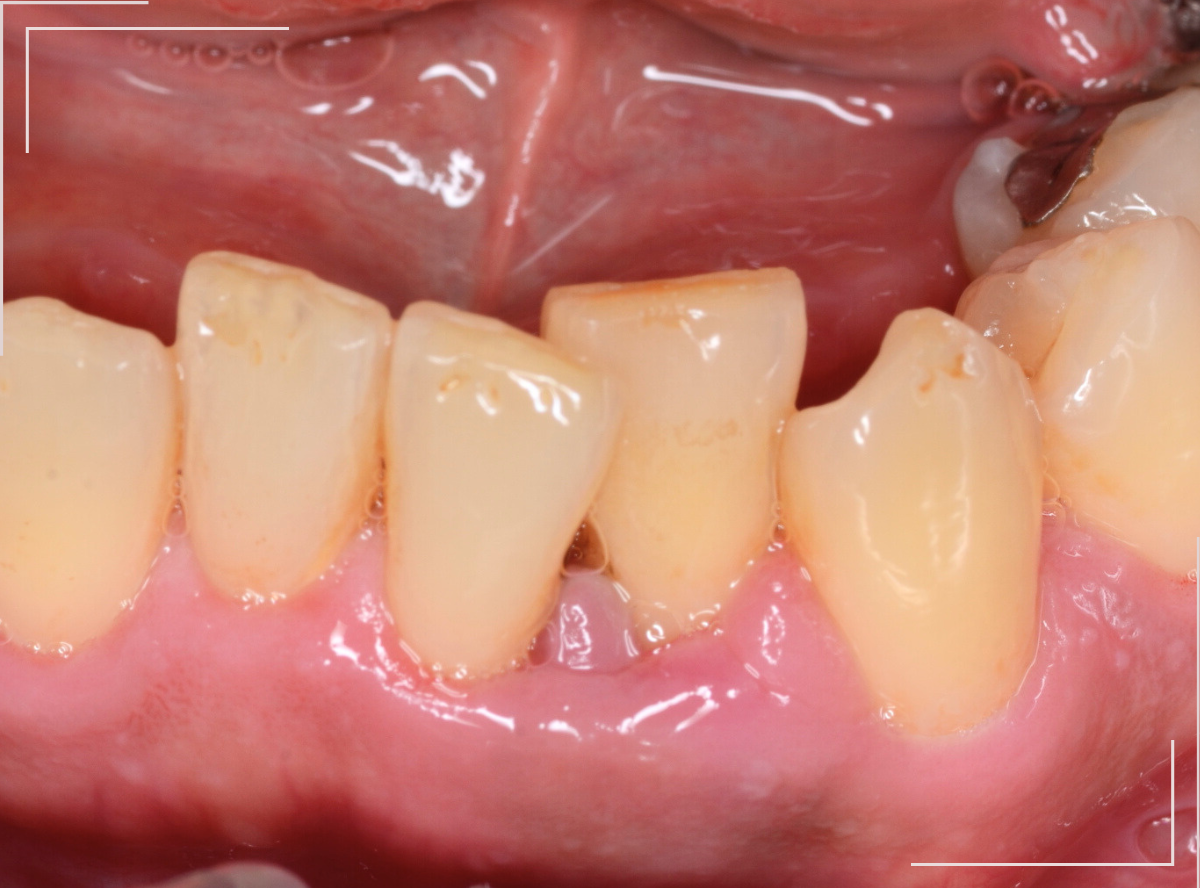

スケーリング・SRP

衛生士さんの仕事の代表格と言えば、何と言っても、スケーリングやSRPといった、P処置です。

まずは、自覚症状の乏しい歯周病の理解を患者さんに広め、治療を行ってください。